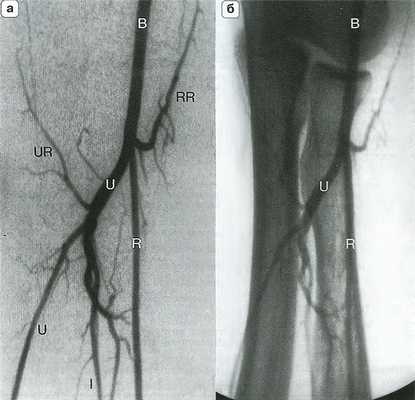

![Рис. 14.4. Артериальная анатомия (а) и костные ориентиры (б) локтевого сустава]()

Рис. 14.4. Артериальная анатомия (а) и костные ориентиры (б) локтевого сустава. Плечевая артерия (В) делится на уровне локтевого сустава на лучевую (R) и локтевую (U) артерии. Межкостная артерия (I) является ветвью локтевой артерии, которая в некоторых случаях продолжается на кисть. RR - лучевая возвратная артерия; UR - локтевая возвратная артерия.